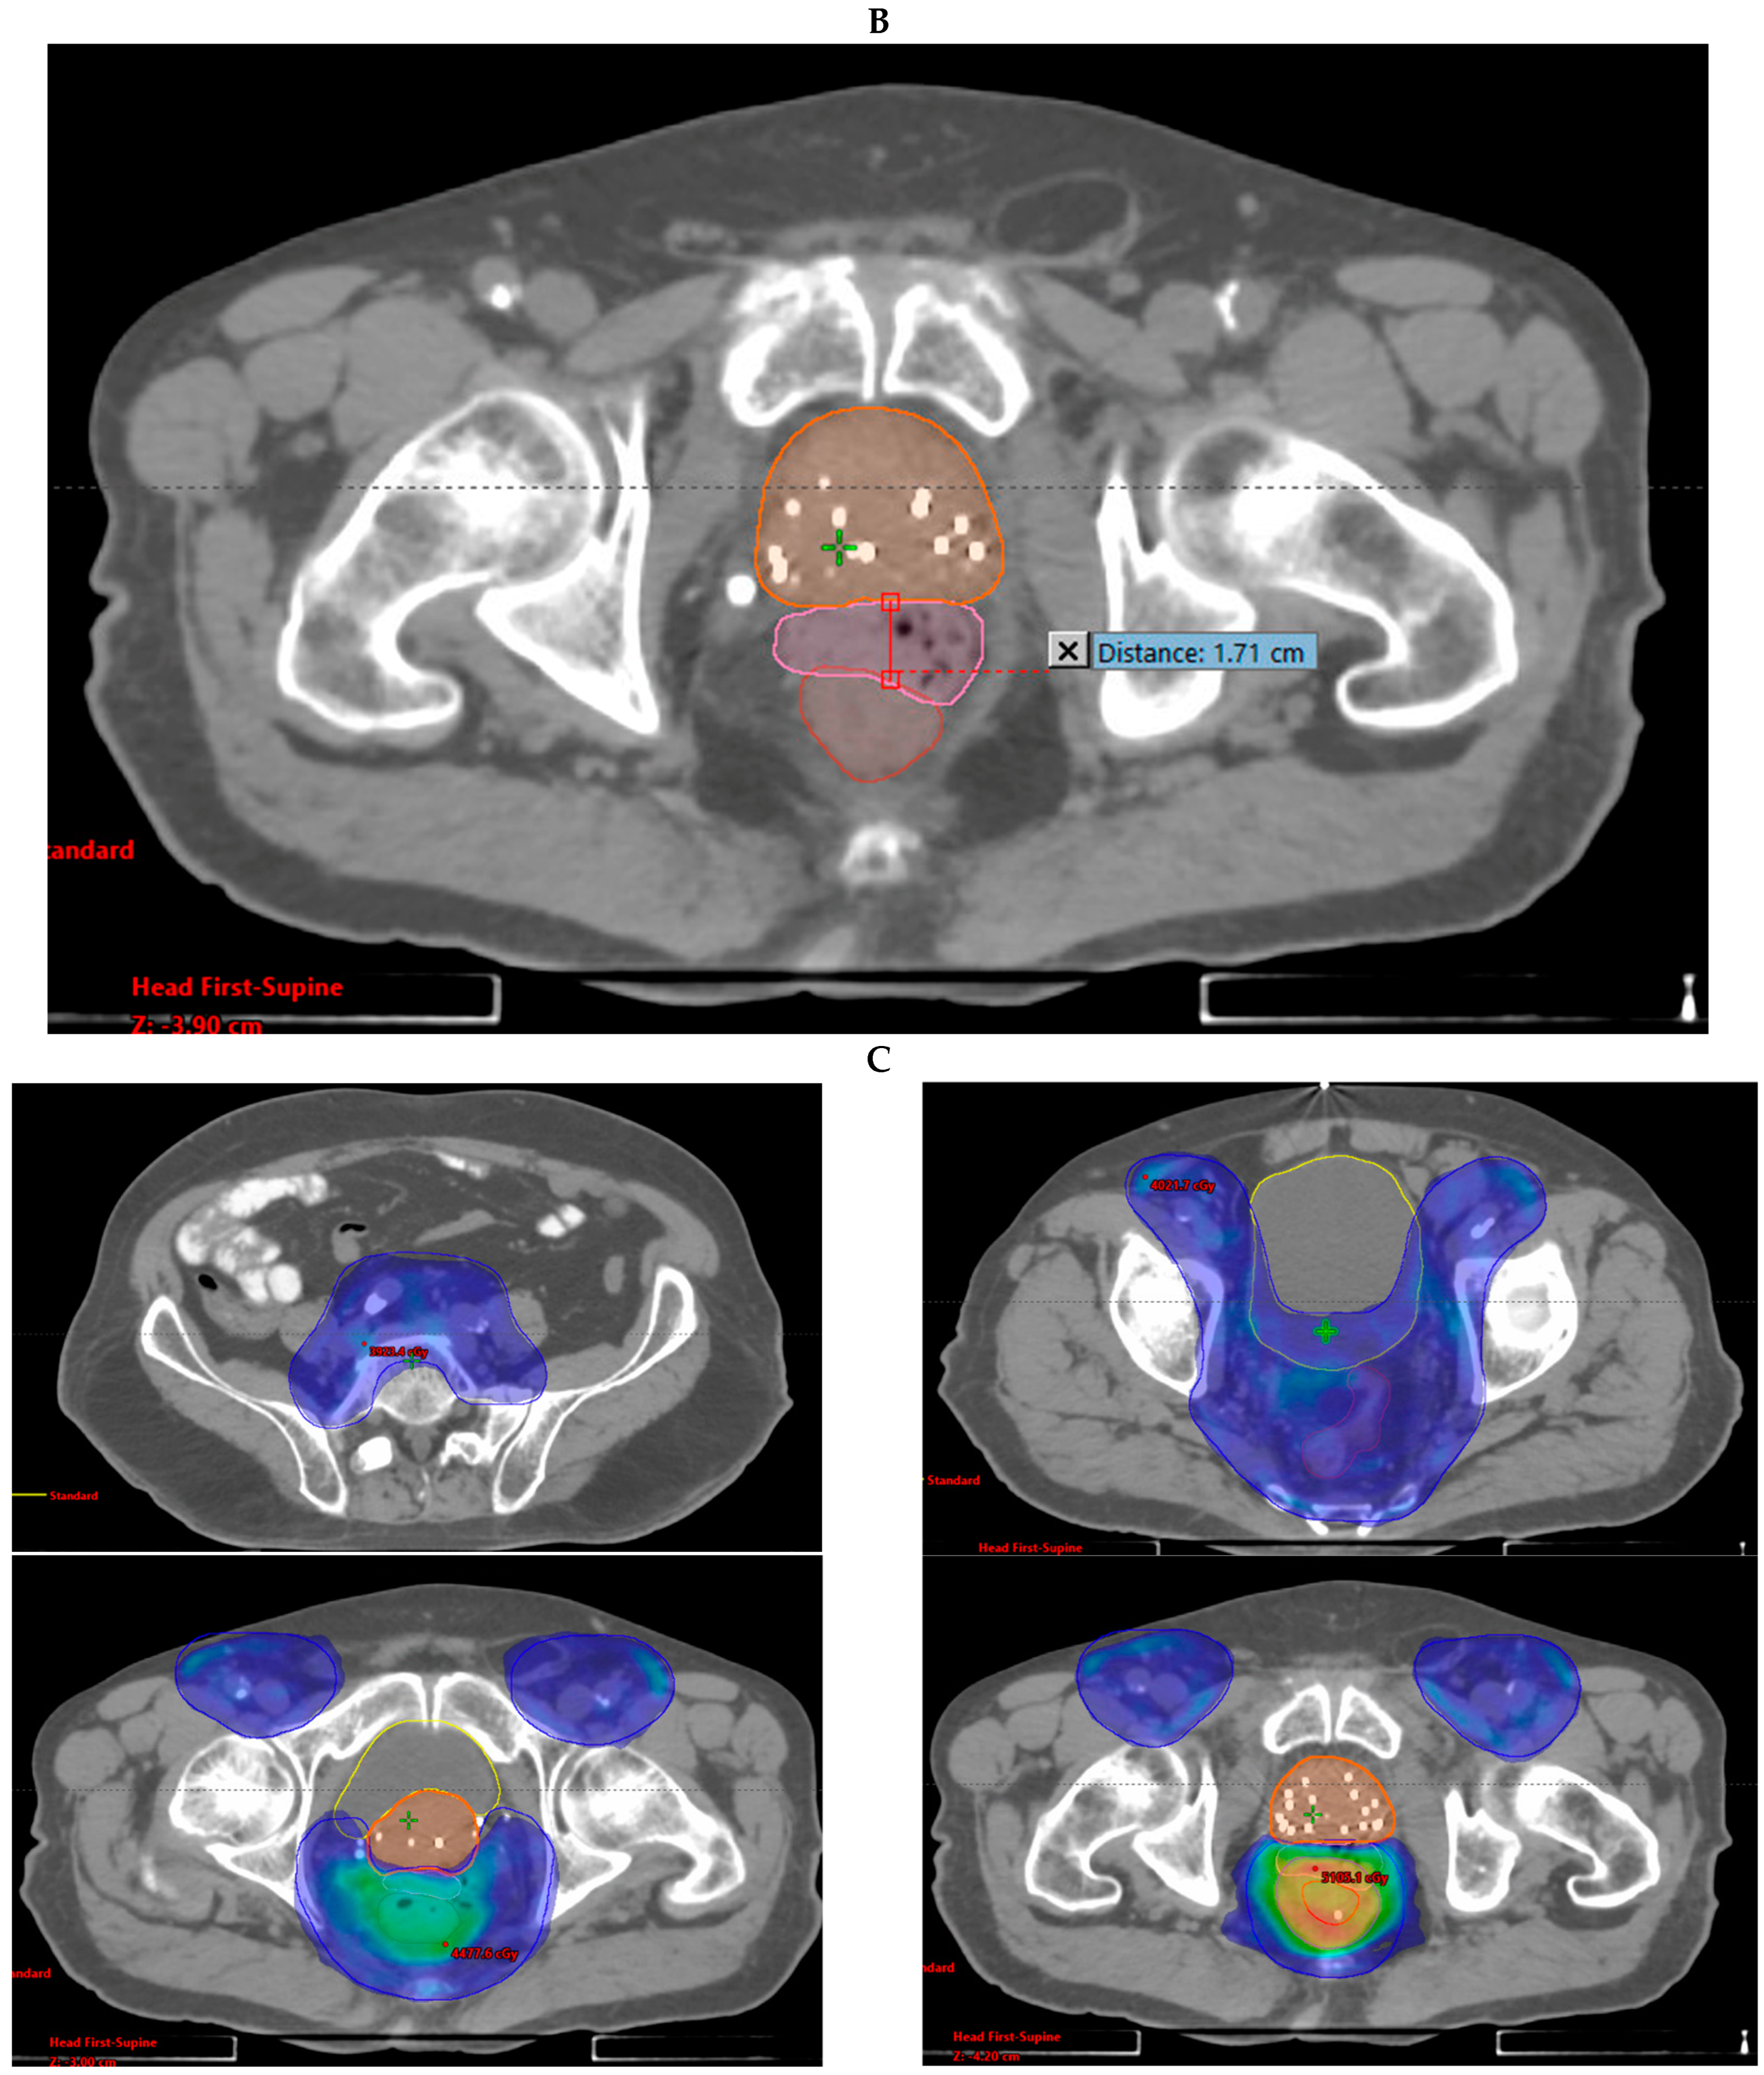

3.1. Case Report 1: Anal Squamous Cell Carcinoma

3.2. Case Report 2: Rectal Adenocarcinoma

| Disease | GTV V100% | PTV V100% | Mean Rectal Dose (cGy) | Mean Bladder Dose (cGy) | Max Distance of Spacer (cm) |

|---|---|---|---|---|---|

| Anal | 100% | 96% | 4024.7 | 2730.1 | 1.71 |

| Rectal | 62% 1 | 73% 2 | 4462.5 | 3957.6 | 1.10 |